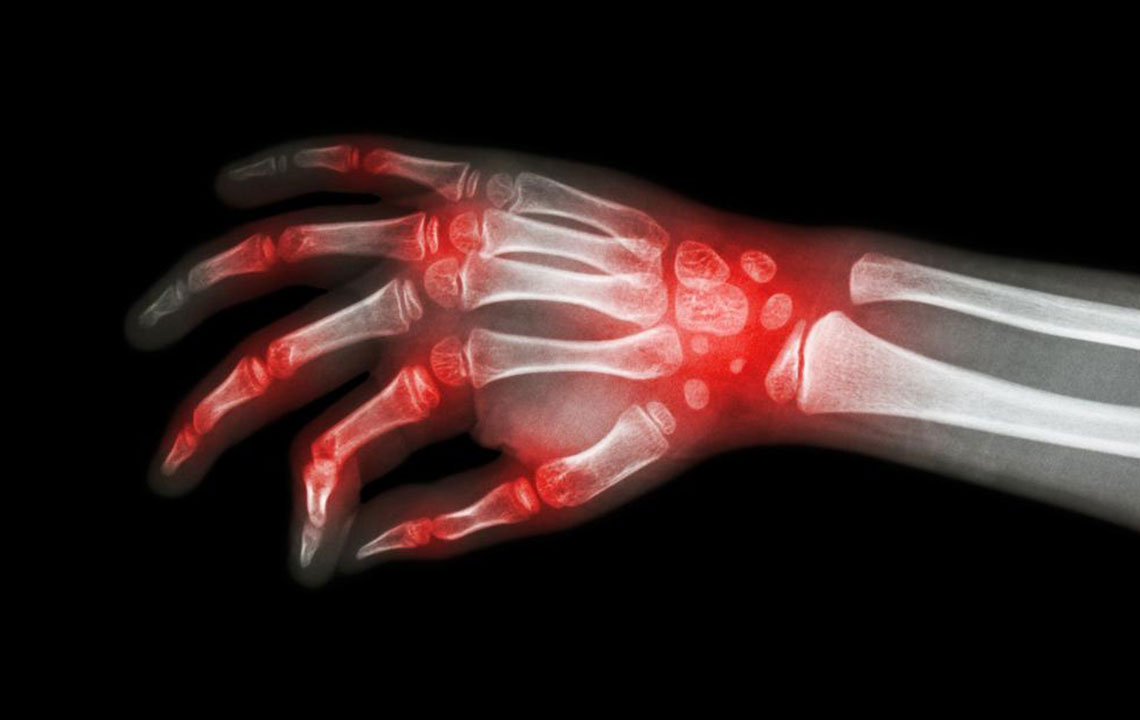

The most shared and evident similarity that rheumatoid arthritis and lupus share is joint pain.

It is these similarities that cause a lot of confusion with the diagnosis of rheumatoid arthritis and lupus. There are several times when patients are diagnosed with rheumatoid arthritis when they actually have lupus. This usually happens in the early stages of the disorder. As the condition progresses, the difference becomes evident; rheumatoid arthritis causes bone deformity and erosion while lupus rarely leads to bone erosion.